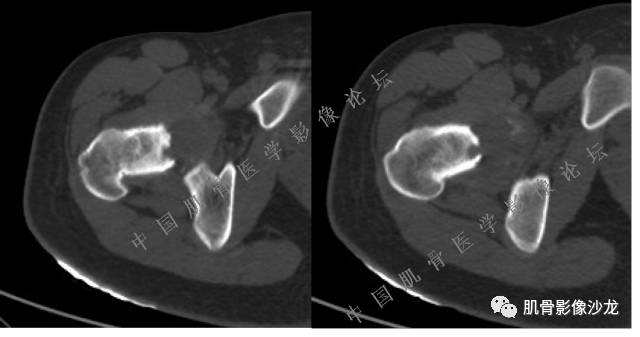

主诉:右髋及右膝部疼痛3月余

现病史:3月前打球时自觉右大腿肌肉拉伤后右髋及右膝部疼痛,自服“活血化瘀”类药物(具体不详)后自觉疼痛缓解,2月前打球时再次扭伤,右髋及右膝部疼痛明显,行走时疼痛加重,自服药物治疗,效果不佳,遂来诊。

医影在线 20:13 干骺端溶骨性破坏,边缘模糊,低密度肿块,似有钙化

Echo 20:13 有骨质破坏,边界不清,有软组织肿块,我觉得恶性是要考虑的

Echo 20:16 软组织肿块突破了骨皮质